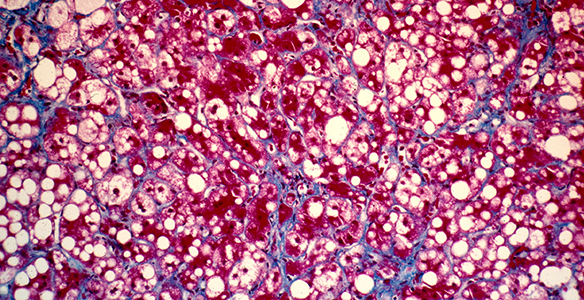

NASH-Fibrose